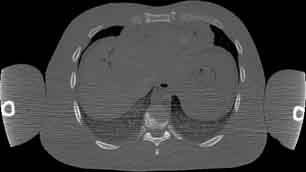

Visible Human male: Sectio transversalis 1488

CT

NMR

Pd                          / T2 \                         T1